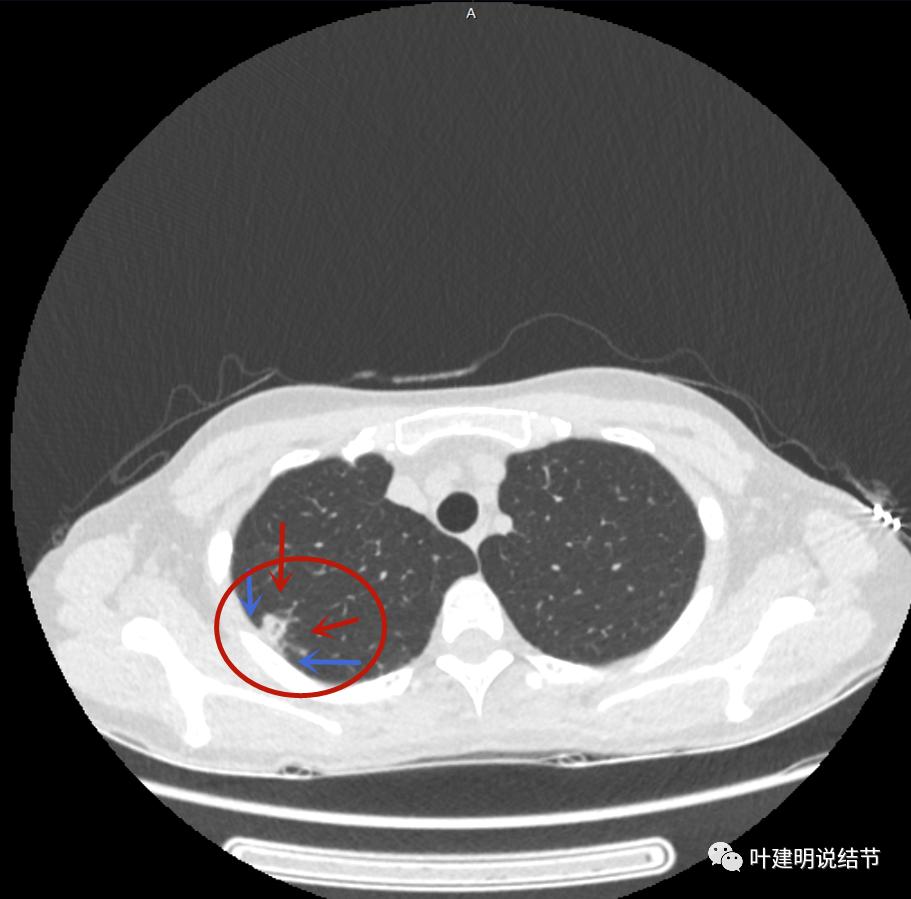

下面是今年复查的平扫片子,来看看有什么变化:

病灶邻近胸膜异常增厚(蓝色箭头)

有卫星灶(绿色箭头),邻近胸膜明显增厚,且模糊,边不清

邻近胸膜增厚

主病灶此层面似三角形,邻近胸膜增厚(蓝色箭头),结节实性部分密度较高(粉色箭头),边缘显模糊(砖色箭头)

上图与恶性较为符合,空洞性病灶,壁厚薄不均,增厚部分还凹凸不平(细红色箭头所指)

上图磨玻璃部分密度过低,且与正常肺组织界限模糊(砖色箭头),粉色箭头示囊壁密度过高的点状,蓝色箭头示邻近胸膜处的增厚

上图也像恶性,但整个囊壁的密度感觉过高了点,边缘磨玻璃淡、散且模糊,邻近胸膜有增厚

上图病灶的边相对比较光,没有毛刺征,邻近胸膜增厚

上图病灶边缘比较平直,没有膨胀性(桔色箭头),旁边的磨玻璃影淡且界限不清,邻近胸膜增厚。

再看影像印象:病灶较1年前有所进展,部分层面像恶性,囊壁厚薄不均,内面有小突起。但邻近胸膜增厚,旁边的磨玻璃部分散且淡,边界不清,实性部分边相对较光,囊壁有点状过高密度。良性可能性大些,恶性不能除外。